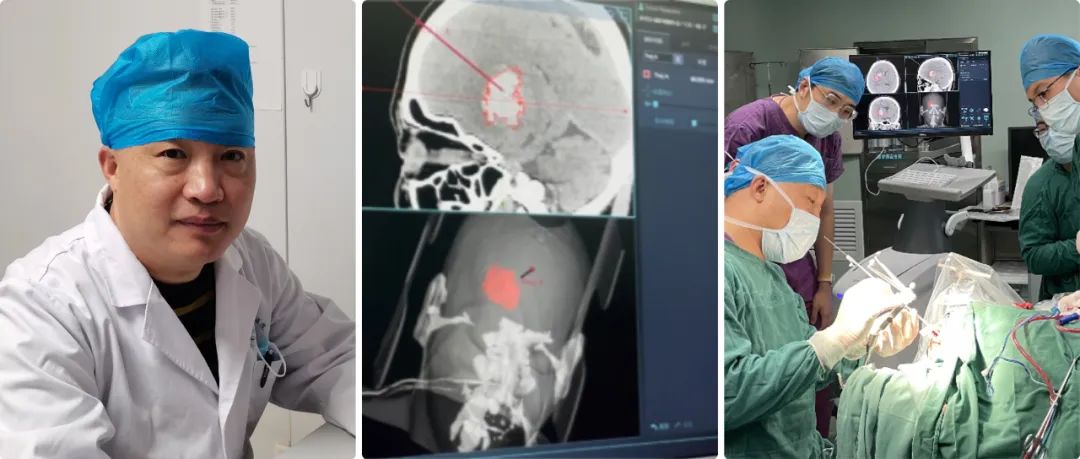

高磊:我院神经外科自1998年正式成立,至今经过二十余年的努力,已成为济南市济阳区人民医院发展最为迅猛的学科之一。科室开放床位45张,其中抢救、监护床位5张。年门诊量5000余人次,年收治患者2600余人次,每年完成各类手术400余台,其中危重的病人手术170-200例左右。

高磊:随着现在交通法规的日益完善,现在颅脑创伤的病人正在逐年的减少,自发性脑出血的病人却在逐年的增多,所以科室也从单纯的颅脑创伤逐步成为集显微神经外科、立体定向神经外科、血管内介入神经外科等多个亚学科的综合性神经外科,下一步以脑血管病为主要救治方向。

但是大部分病人虽然是脑出血,但是病人生命体征比较稳定,我们尽可能用神经导航来实现微创血肿穿刺引流。

神经导航微创手术就避免了传统开颅手术的弊端,它可以实现精准穿刺血肿引流,病人一次性接受手术,恢复比较快,并对病人整体创伤很小。

高磊:准备做神经导航手术之前,我们给患者进行颅脑CT薄层扫描,层厚大约在0.625毫米-1毫米,然后在神经导航系统进行重建,在重建虚拟像上选择合适的靶点。

靶点选择的三个原则:第一,从头皮到血肿的穿刺路径比较短;第二,避开大脑重要功能区;第三避开重要的神经血管。

我们经过对病人注册,实现在电脑上与实际人头部位置融合,再根据电脑上确定的穿刺位置,选择实际病人颅上的穿刺位置,两者基本上重合,这样确保穿刺路径的精准性。

高磊:任何手术设备,尤其导航系统,漂移不可避免;Sinovation神经导系统的误差可以控制在0.5毫米左右。

我们对脑组织等漂移怎么克服呢?第一精准定位,第二实时导航,就是穿刺点确定后,我们通过颅骨钻孔到达皮层,再进行一次注册和校正偏差,确保漂移减到最小的程度。